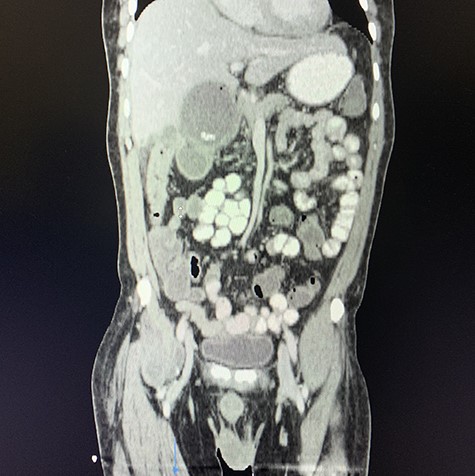

A computed tomography (CT) scan of the abdomen revealed an enlarged, thickened gallbladder with multiple stones, communicating with an intrahepatic collection in segment 4 measuring 116 × 80 mm, with an associated air fluid level and air locules (Fig. 1). There was an apparent fistulous tract to the hepatic flexure of the colon, another large collection in segment 6 (97 × 96 mm) as well as other smaller collections (Figs 2 and 3).

Coronal view of oral and intravenous contrasted CT scan of the abdomen demonstrating features of cholecystitis with fistulous communication with the hepatic flexure of the colon with associated pneumobilia.